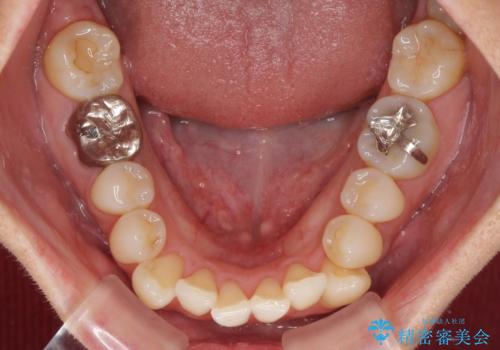

- 八重歯と、それによる口元の膨らみを気にして来院された患者様です。

八重歯・デコボコの解消とともに、前方に張り出した上顎前歯を引っ込めることを目的とし、上下左右の第一小臼歯4歯を抜歯をしてワイヤー矯正により治療することとしました。

半年もしないうちに八重歯は解消し、治療も当初予定通り2年強で終えることができました。